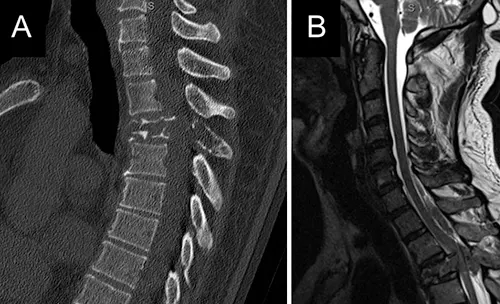

- Direct Invasion/Destruction: Primary bone tumors (like osteosarcoma) or metastatic tumors directly destroy bone tissue [3].

This accelerated bone resorption is a key mechanism leading to complications like pathological fractures (fractures occurring with minimal or no trauma due to weakened bone) and pain [2, 3]. Vertebral bodies are common sites for metastases and myeloma, and pathological compression fractures here can cause spinal cord or nerve root compression, representing neurological emergencies [3].

| Osteomyelitis | Focal bone destruction (lysis), periosteal reaction, sequestrum/involucrum (chronic). Often localized pain, swelling, fever. | Elevated WBC, ESR/CRP. Blood/bone cultures positive. MRI most sensitive early. X-ray changes lag. Bone scan positive. |